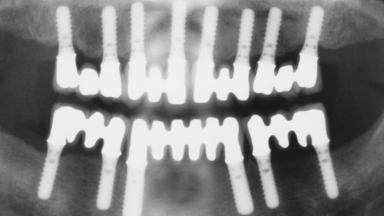

Immediate Loading of Eight Implants in the Maxilla and Six Implants in the Mandible and Final Restoration with Three-Unit and Four-Unit FDPs

# of Implants 14

Type of Implants One-Piece

Modality 6+ implants with immediate loading